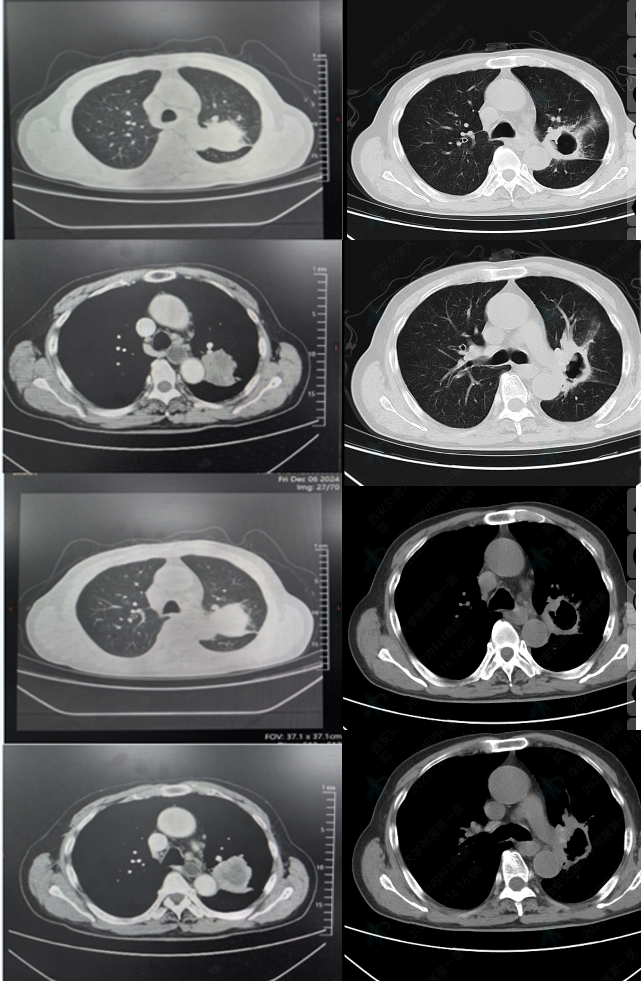

• 2024-12-6胸部CT:左肺肿物

图1 2024-12-6胸部CT

2025-1-17 首次用药后,胸部CT结果如下,提示病灶明显缩小;

图7 2024-12-6(左)对比2025-01-17(右)胸部CT

2025-04-26 用药5周期后,胸部CT结果如下所示,疗效评估为PR

图8 2024-12-6(左)对比2025-04-26(右)胸部CT

2025-6-16 用药7周期后,胸部CT结果如下所示,疗效评估为PR

图9 2024-12-6(左)对比2025-06-16(右)胸部CT

截止最新随访时间(2025-09-12),该患者持续PR,目前仍在接受“依沃西单抗联合化疗”方案治疗。